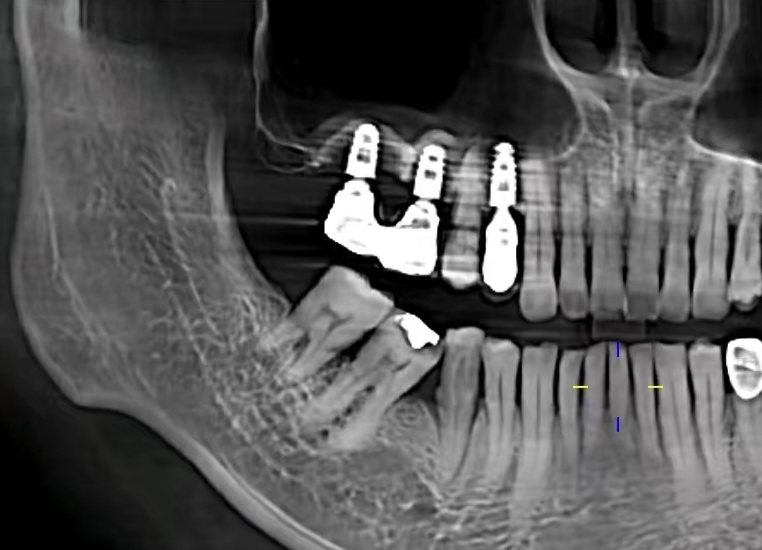

It is recommended that reconstruction is necessary, otherwise the adjacent teeth will tilt to the left and right, and the antagonistic teeth will extend toward the missing teeth.The back teeth cannot be seen, so why do they need reconstruction?To answer the above situation, why is reconstruction necessary if only the second molar is missing? Since the back teeth cannot be seen, why do we need to fill them? That is because the corresponding opposing teeth will extend towards the missing teeth, thus creating a height difference. If the teeth are not straight, there will be a blind spot for cleaning, which will almost always cause new caries on the adjacent teeth. . In addition, when the second molar extends toward the missing tooth, it is easy to cause the tooth root to be exposed, resulting in sensitivity and discomfort. Therefore, even if the back teeth are not visible, they still need to be treated in this situation to avoid subsequent problems.

In order to chew smoothly, teeth have the characteristic of being close to each other. Therefore, if the teeth are left unattended after extraction, the teeth on the opposite side will extend and grow towards the missing teeth area, and the adjacent teeth on the left and right will also gather towards the missing teeth area, causing irregular teeth. Condition.

Problem 4: Alveolar bone atrophy